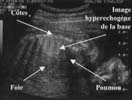

Séquestration pulmonaire : c'est le principal diagnostic différentiel de la MAKP. Les deux malformations sont en fait souvent associées au sein d'une même lésion [4, 13], et leur diagnostic n'est pas capital car il ne modifie pas profondément la prise en charge post-natale [5]. Le principal critère du diagnostic de la séquestration est la mise en évidence d'une vascularisation de la lésion par une artère aberrante naissant de l'aorte.

Masse hyperéchogène siègeant dans le base pulmonaire. Triangulaire si extra-lobaire, ronde si intra-lobaire.